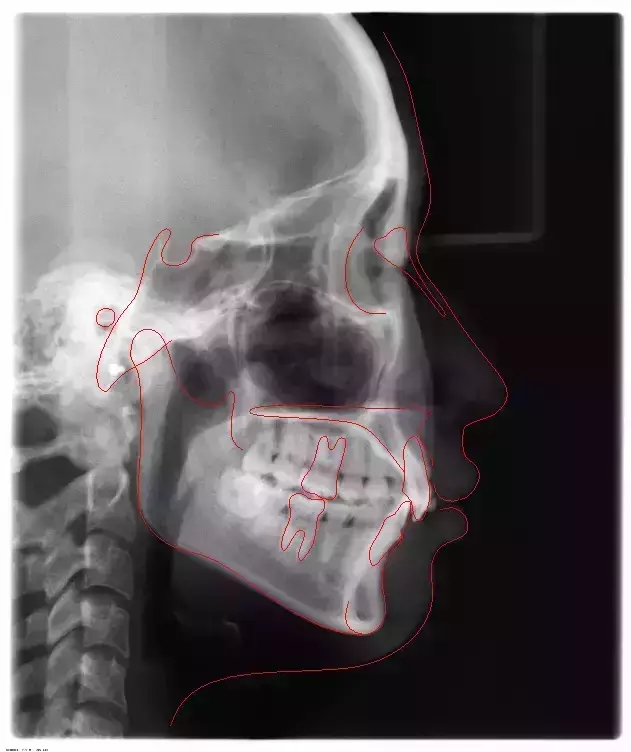

Damon 病例分享:安氏 II 類二分類露齦笑的矯治(董一磊)

患者信息